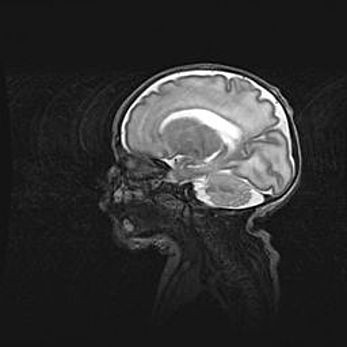

Аномалия Денди-Уокера. Признаки гипоплазии мозолистого тела.

Возраст: 5 месяцев 3 дня

Вес: 5550 г

Пол: мужской

Окружность головы: 39 см

Срок гестации: 40 недель

Аномалия Денди-Уокера – это порок развития головного мозга, для которого характерна триада симптомов: гипотрофия или аплазия червя мозжечка и/или полушарий мозжечка, расширение четвёртого желудочка с формированием ликворной кисты задней черепной ямки, гипертензионная гидроцефалия различной степени.

Гипоплазия мозолистого тела относится к дефектам внутриутробного этапа развития мозговой ткани, возникающим в процессе закладки структур головного мозга, что происходит на начальных этапах развития эмбриона.